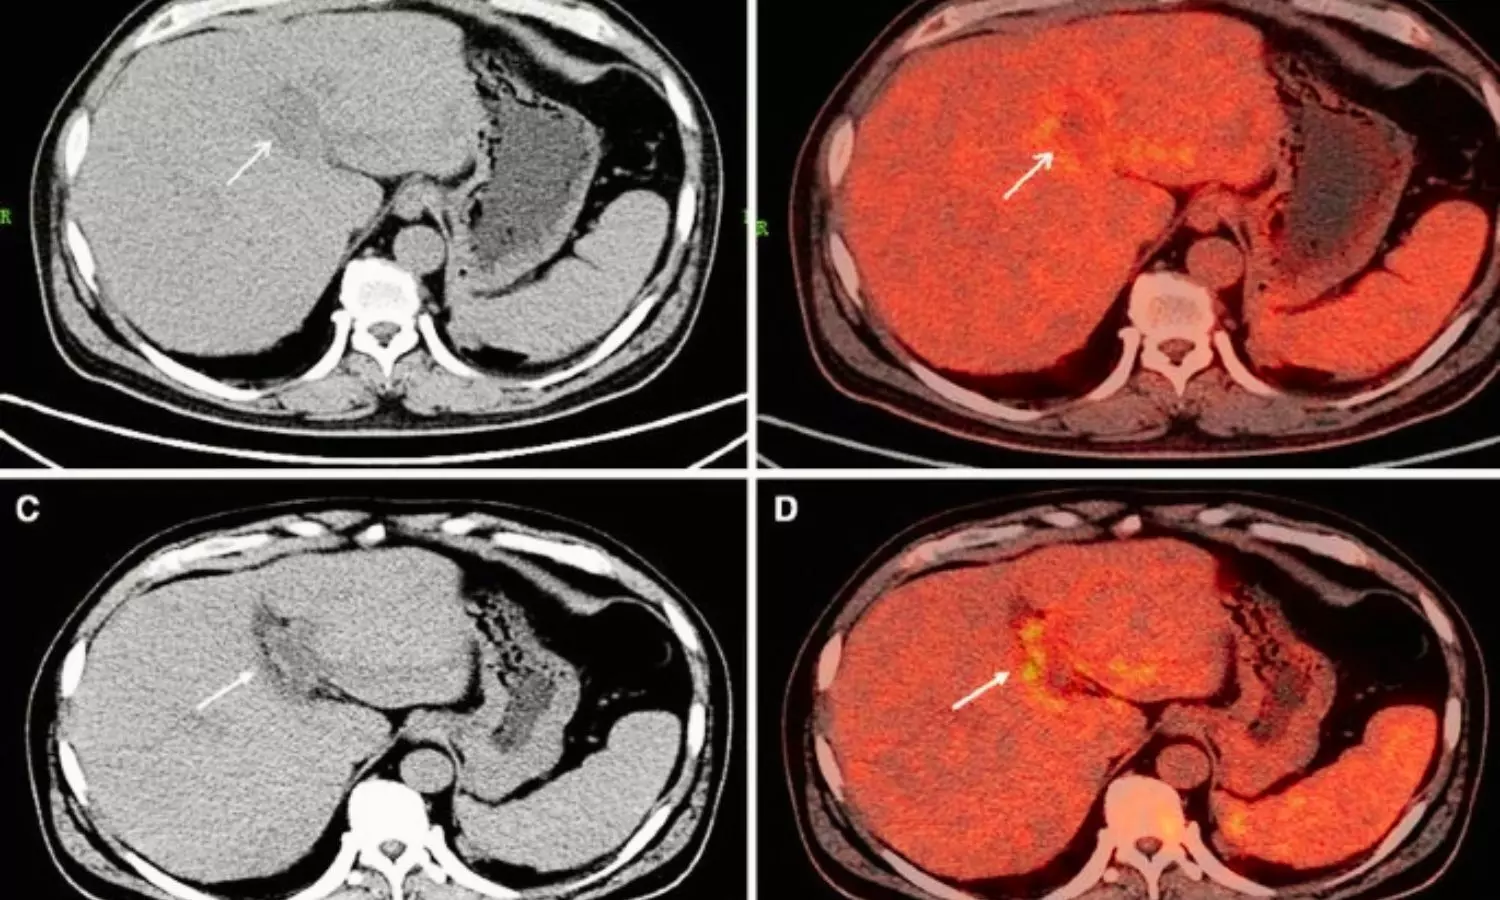

A new study published in the Nature Scientific Reports showed that the investigation of novel therapeutic targets may result from the connections between metabolic activity and a number of inflammatory factors.Engineered Stone (ES) silicosis, a serious occupational health problem and is highly prevalent due to the introduction of new materials for kitchen countertops and bathrooms. It is unknown what metabolic processes take place in the lungs and adenopathies, and how they relate to systemic inflammation. Thus, the objective of this study was to evaluate the metabolic activity of lymph nodes and lung lesions in patients with ES-related complicated silicosis and look into how these metabolic activities relate to particular biomarkers, systemic inflammatory indices, and peripheral blood lymphocyte subpopulations.This study included patients with complex silicosis. The patients had all been engaged in finishing and installing engineered stone for at least 5 years, and they had all been away from these working circumstances for at least 7 years. Blood samples, pulmonary function tests, positron emission tomography/computed tomography employing 18F-fluorodeoxyglucose (18F-FDG PET/CT), and clinical data measures were all carried out.The patients were 44 ± 5.4 years old on average. Additionally, the average number of years from exposure cessation was 11.6 ± 1.6 years, and the average exposure length was 10.94 ± 3.2 years. The average maximum standardized uptake value (SUVmax) of significant opacities was 6.32 ± 3.Hypermetabolic mediastinal lymphadenopathies were seen in all of the patients, and extrathoracic lymphadenopathies were seen in 88.2% of the patients. Fibrinogen (ρ = 0.717, P = 0.001), the lymphocyte-to-monocyte ratio (ρ = -0.506, P = 0.038), the systemic inflammatory response index (ρ = 0.559, P = 0.02), and CD4+NKT cells were all associated with the SUVmax of the big opacities. Years after the end of silica exposure, large regions of lung opacity and lymphadenopathies showed elevated metabolic activity.Overall, even years after exposure has stopped, ES silicosis causes severe metabolic activity in the lungs as well as in thoracic and extrathoracic lymphadenopathies. Given that silica is a Group 1 carcinogen and may cause lung cancer to coexist, it's critical to comprehend the topographic distribution of hypermetabolic lymphadenopathy linked to silica exposure in order to prevent PET from overstaging neoplastic processes. Source:León-Jiménez, A., Rodríguez-Rubio Corona, J., Jiménez-Gómez, G., Piñero Fernández-Reyes, M. L., Hidalgo-Molina, A., Pajares-Vinardel, M., Conde-Sánchez, M. Á., Campos-Caro, A., & Sanchez-Morillo, D. (2025). High metabolic activity in positron emission tomography and systemic inflammation occurring years after exposure cessation in engineered stone silicosis. Scientific Reports, 15(1), 25364. https://doi.org/10.1038/s41598-025-10562-5